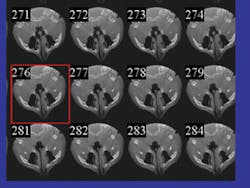

The CBCT scanner acquires hundreds of slices per rotation (see Figure 4). Once obtained, the computer processes these slices by assembling them into a full cylinder-shaped volume analogous to a stack of compact discs. The various proprietary software applications compress and compile the data into the DICOM format for use in the various applications.